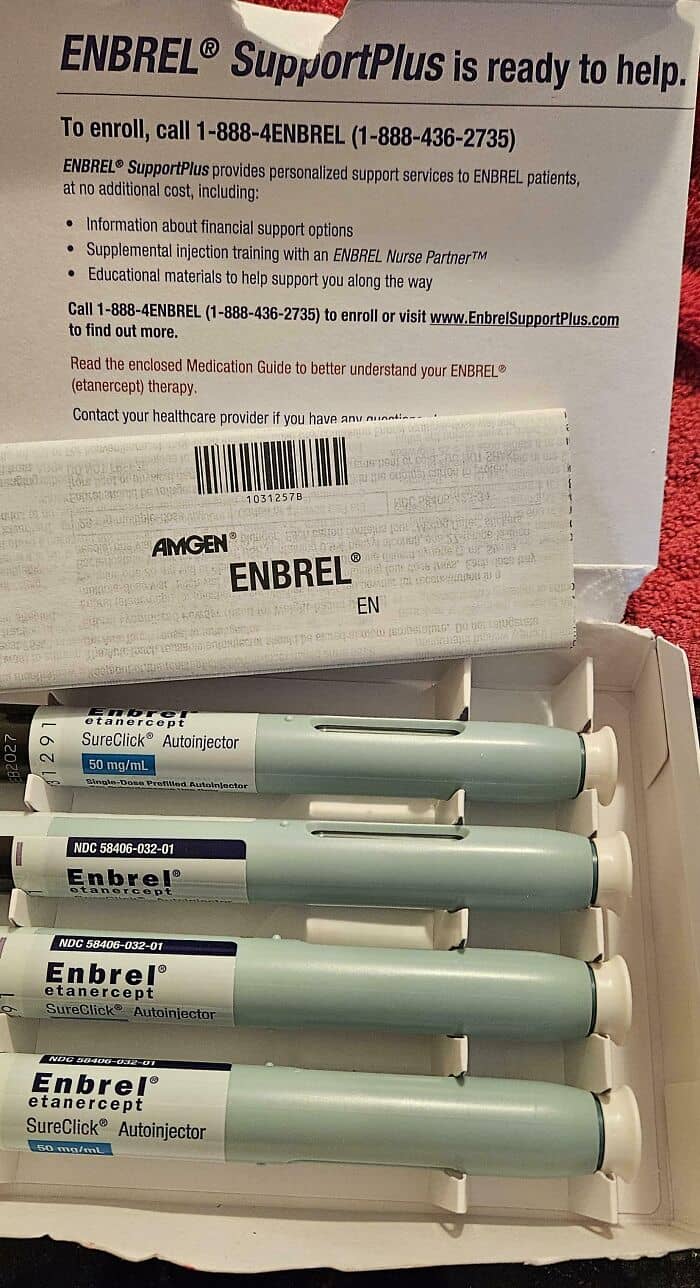

#12 $7,000/Month Gets You 4 Pokes In The American Medical System (Psoriatic Arthritis)